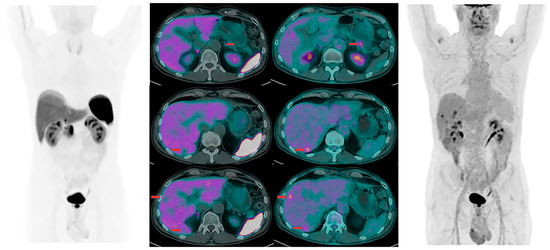

- Kayani, I.; Bomanji, J.B.; Groves, A.; Conway, G.; Gacinovic, S.; Win, T.; Dickson, J.; Caplin, M.; Ell, P.J. Functional Imaging Of Neuroendocrine Tumors With Combined 68Ga-DOTATATE (Dota-DPhe1,Tyr3-octreotate) and [18F]FDG PET/CT. Cancer 2008, 112, 2447–2455. [Google Scholar] [CrossRef] [PubMed]

| Functional Imaging Of Neuroendocrine Tumors With Combined 68Ga-DOTA-TATE (Dota-DPhe1,Tyr3-octreotate) and [18F]FDG PET/CT | The role of the 2 tracer may be complementary in mapping patients with metastatic tumors. | [42] |